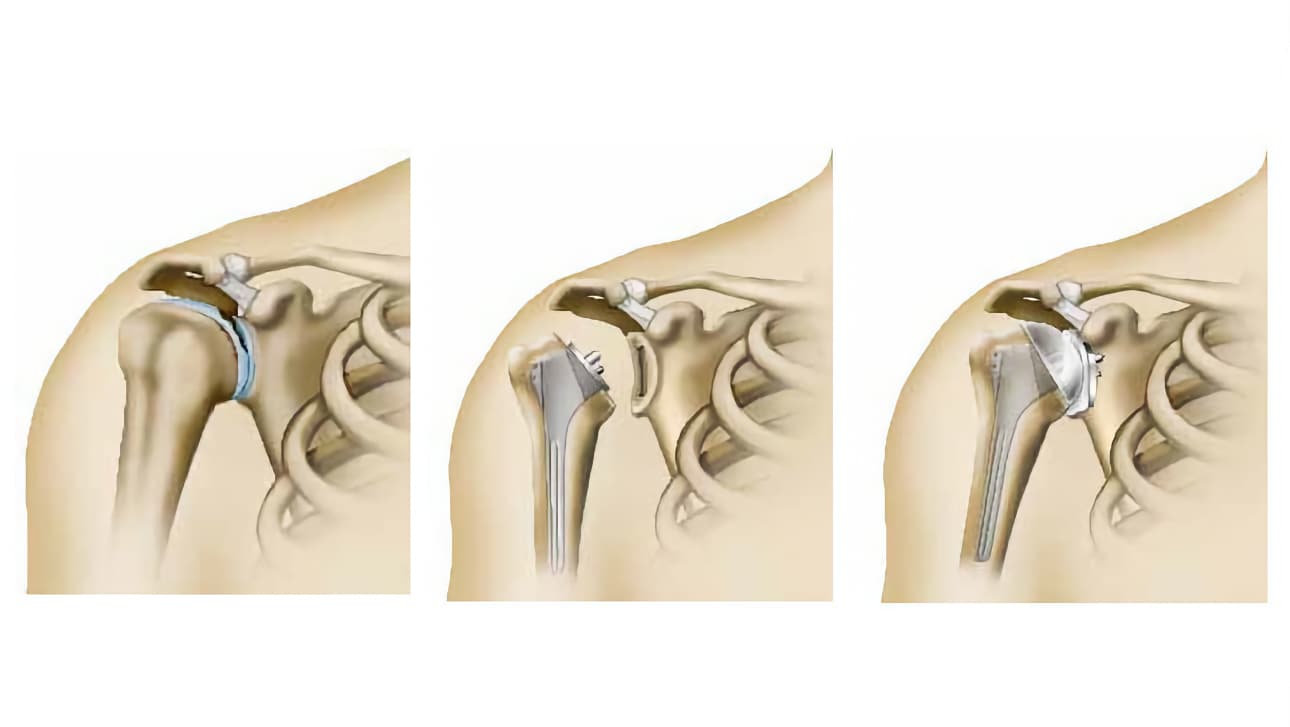

Πρόκειται για την αφαίρεση των περιοχών της άρθρωσης που έχουν φθαρεί και την αντικατάστασή τους με ένα ή περισσότερα τεχνητά μέρη ανάλογης μορφής (πρόθεση). Η επέμβαση αυτή επιτρέπει την ανώδυνη κίνηση του ώμου.

Ανάλογα με την περίπτωση, είναι δυνατό να αντικατασταθεί είτε μόνο η κεφαλή του βραχιονίου ( πρόθεση βραχιόνιας κεφαλής), είτε και τα δύο μέρη της άρθρωσης, δηλαδή η κεφαλή του βραχιονίου και η ωμογλήνη (ολική πρόθεση).

Εάν αντικατασταθεί μόνο η κεφαλή του βραχιονίου, μιλάγε για πρόθεση βραχιόνιας κεφαλής. Αποτελείται από το στέλεχος της πρόθεσης (στυλεός), το οποίο εισάγεται στο βραχιόνιο. Στο στέλεχος εφαρμόζει ένα τμήμα, ανάλογης μορφής με την κεφαλή του βραχιονίου (η κεφαλή πρόθεσης).

Εάν αντικατασταθεί και η ωμογλήνη, μιλάμε για ολική πρόθεση. Εκτός από τα τμήματα που έχουν τοποθετηθεί στο βραχιόνιο, προστίθεται ένα ακόμα μέρος που ονομάζεται κυπέλλιο και τοποθετείται στη θέση της ωμογλήνης.